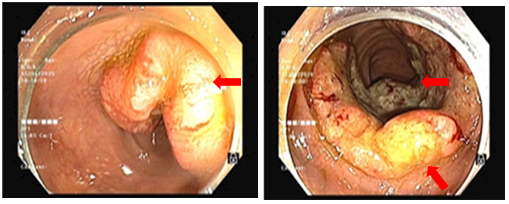

-         Nội soi đại trực tràng (06/2025): Trực tràng: Cách rìa hậu môn ~ 1cm có khối sùi loét chiếm 4/5 chu vi trực tràng. Cách rìa hậu môn ~ 10 cm có sùi loét chiếm 3/4 chu vi trực tràng. Niêm mạc trực tràng còn lại có vài polyp kích thước ~ 0.2 - 0.5 cm

Hình 3: Tổn thương tại 2 vị trí trực tràng: Cách rìa hậu môn ~ 1 cm có khối sùi loét chiếm 4/5 chu vi trực tràng. Cách rìa hậu môn ~ 10 cm có sùi loét chiếm 3/ 4 chu vi trực tràng.

- Nội soi đại trực tràng (09/2025): Đại tràng sigma có 04 polyp kích thước ~ 0.5-1.5cm, polyp lớn nhất có cuống. Đoạn cuối đại tràng sigma có khối loét sùi chiếm 1/2 chu vi (Sinh thiết 03 mảnh- Ống 2) Trực tràng: Cách rìa hậu môn ~7.0cm có loét sùi lớn chiếm 3/4 lòng trực tràng (Sinh thiết 03 mảnh - Ống 1).

Hình 5: Bên trái (trước điều trị): Khối u trực tràng dạng sùi, kích thước lớn, chiếm gần hết chu vi lòng trực tràng. Bề mặt khối u gồ ghề, loét, dễ chảy máu. Bên phải (sau điều trị): tổn thương sùi giảm kích thước rõ rệt, bề mặt u phẳng hơn, xơ hóa và loét nông, phủ giả mạc trắng, lòng trực tràng mở rộng hơn -> khối u đáp ứng một phần

-       Lâm sàng: triệu chứng rối loạn đại tiện cải thiện rõ rệt, không còn tình trạng đi ngoài nhiều lần.

-       Nội soi đại trực tràng: so với trước điều trị, khối u thu nhỏ kích thước đáng kể,từ tổn thương sùi loét chiếm gần toàn bộ chu vi trực tràng, sau điều trị lòng trực tràng được mở rộng, ít còn dấu hiệu tắc nghẽn -> phù hợp đáp ứng một phần.